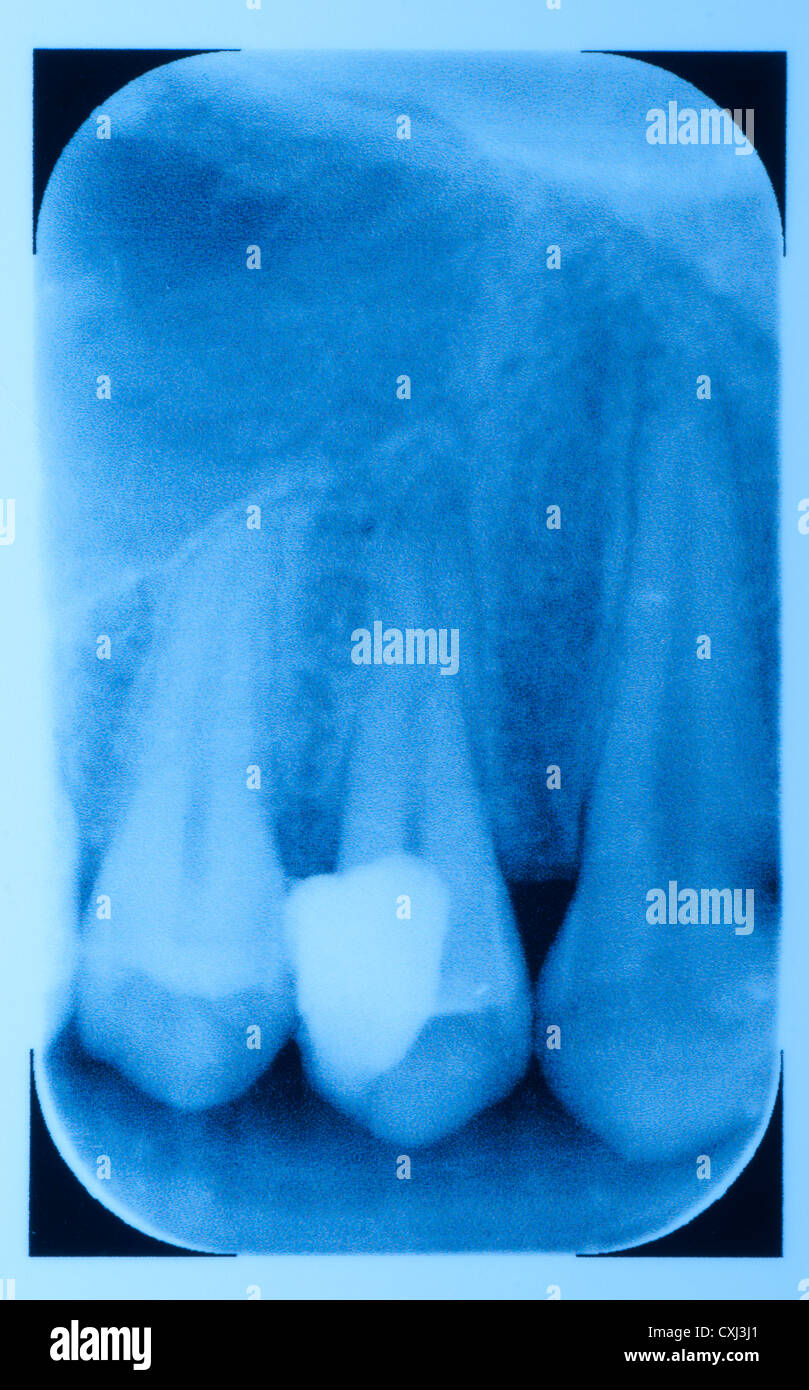

Dental Fracture X Ray . odontoid process fracture, also known as a peg or dens fracture, occurs where there is a fracture through the. dental fractures are often clinically apparent but can be overlooked in cases with associated facial fractures, especially as. gaining knowledge of which imaging protocol to use, the relevant anatomy of the teeth and related structures, and the key imaging findings of. There are multiple indications for this type of radiograph including yet not limited to: root fractures are a type of dental damage with unfavourable prognosis, 1 which increases the importance of.